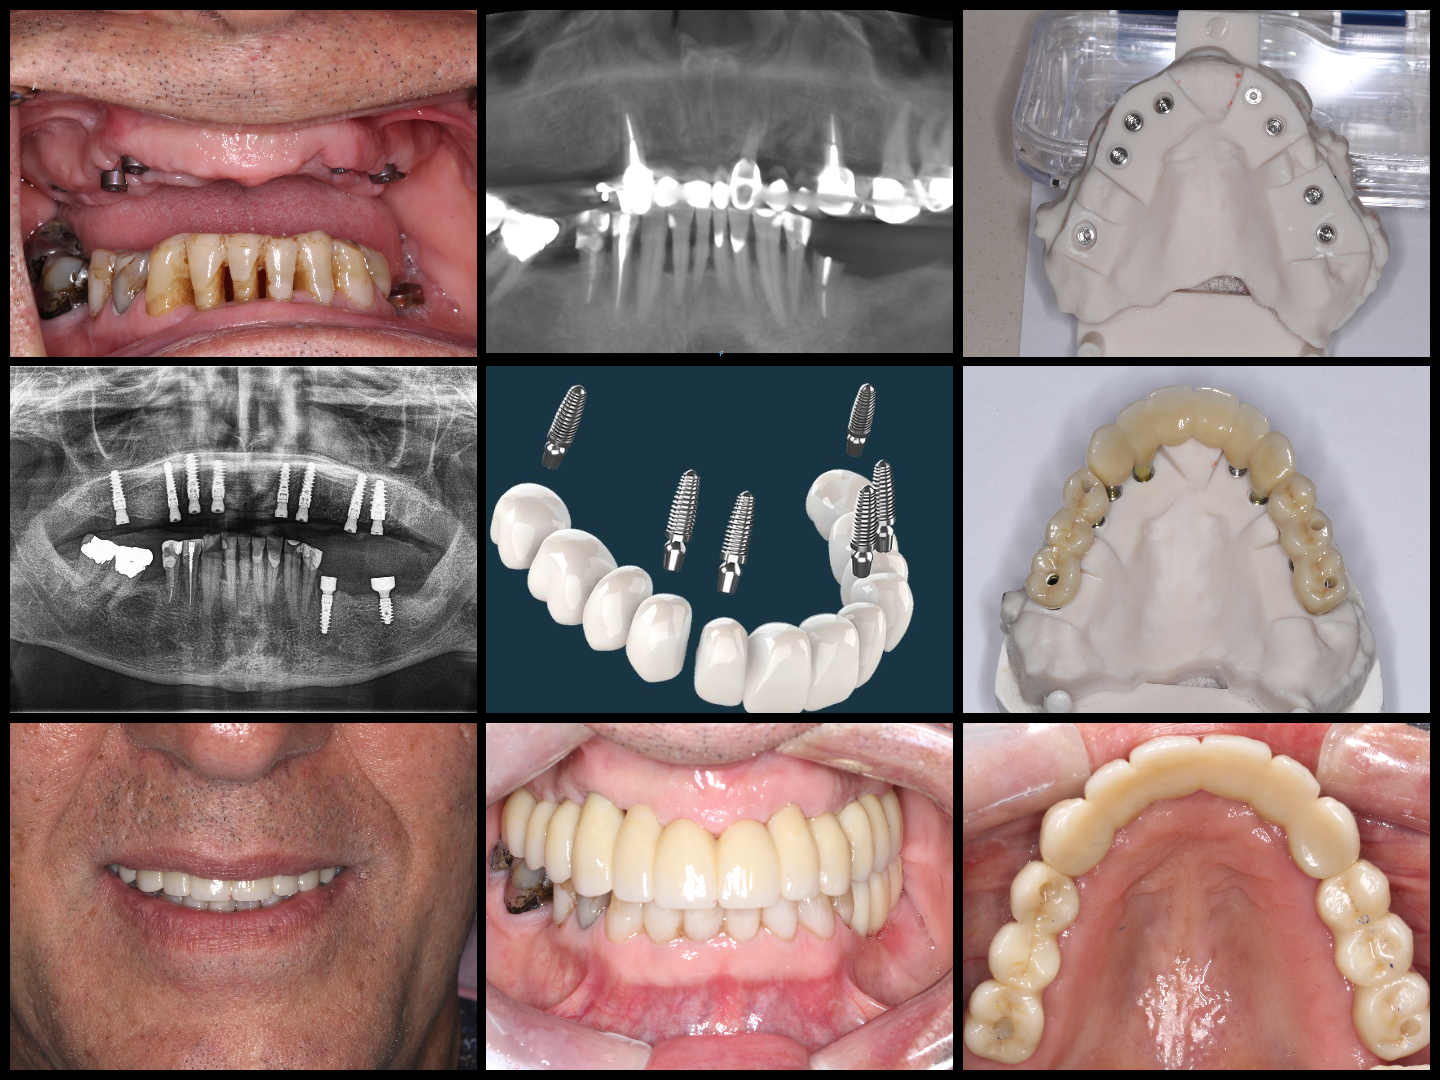

Before & Afters of Dental Implant Patients

Complete Dental Implant Cases Gallery

• When replacing several teeth or all of your teeth, a fixed bridge is anchored to your dental implants. A bridge is a dental restoration that replaces one or more missing teeth by spanning an area that has no teeth. The bridge is held firmly in place by dental implants on each side of the missing tooth or teeth.

General Disclaimer: The results in the photographs are examples only and do not imply any certainty of the result of a procedure, and all outcomes are subject to the circumstances of the individual patient.